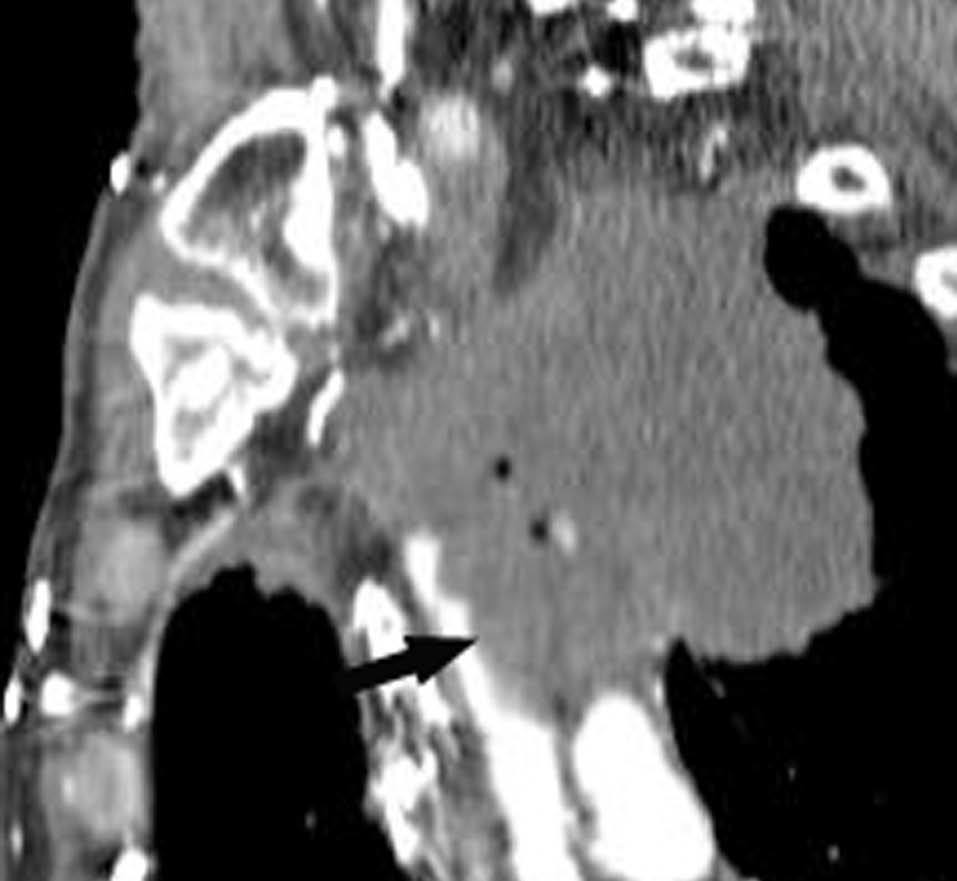

Una ventaja adicional de la TCMC es la capacidad de realizar, como parte del estudio de extensión, una angiografía TC (angioTC) en los tumores de localización central candidatos a cirugía y, fundamentalmente, en aquellos pacientes con hemoptisis que podrían ser subsidiarios de embolización terapéutica. El estudio vascular permite tener un excelente mapa para la cirugía, que ayuda enormemente al cirujano a la hora de planificar la intervención (fig 8). En los pacientes con hemoptisis amenazante, la demostración de una arteria sistémica hipertrófica sirve de guía para la arteriografía y subsecuente terapia endovascular (fig. 9).

Fig. 9.--Hemoptisis masiva secundaria a neoplasia de pulmón. (A) Corte axial con contraste que muestra el origen de la arteria bronquial derecha en la aorta descendente. (B) Reconstrucción de volumen en la que se pone de manifiesto la localización exacta de la arteria bronquial derecha hipertrófica y su exquisita correlación con la angiografía selectiva (C).